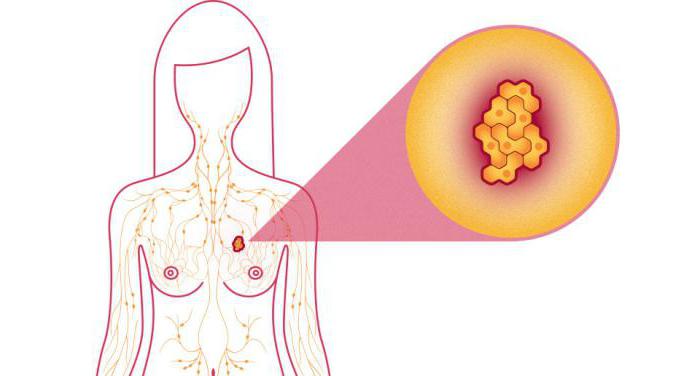

Для початку будемо розбиратися в тому, що це за недуга. Лікарі кажуть, що рак грудей у жінок на 3 стадії – це досить велика пухлина. В діаметрі вона сягає п’яти сантиметрів, при цьому може поширюватися на шкіру: епідерміс темніє, набрякає, приймає форму лимонної кірки. У лімфатичних вузлах в області пахв є метастази: вони спаяні і щільні, значно збільшені в розмірах. Пухлина на перших двох стадіях часто залишається непоміченою, тому жінка звертається до лікаря, коли хвороба вже активно прогресує.

Це дуже небезпечні для здоров’я і життя освіти, які нерідко зустрічаються на останніх стадіях хвороби, коли у жінки діагностують рак молочної залози. Метастази – ті ж пухлинні клітини, що за допомогою струму лімфи (а він дуже розвинений у грудних тканинах) розносяться в лімфатичні вузли. Початкові злоякісні утворення вражають в першу чергу пахвові, підлопаткові і підключичні ділянки тіла. Потім метастази розповзаються в зону шиї, другу груди і область навколо неї. Іноді метастази з’являються раніше, ніж був виявлений сам рак. В цьому випадку потрібно негайно провести всі обстеження, щоб виключити ракове ураження молочної залози.

Гематогенним шляхом – через кровоносну систему – метастази потрапляють в інші органи, де починають паразитувати. Зазвичай вони розташовуються в головному мозку, печінці, легенях, плеврі, кісткових тканинах. Якщо освіти зачепили скелет, то, швидше за все, вони осядуть» в області тазу, на черепі, хребті, ребрах, стегнових та плечових кістках. У цьому випадку жінка відчує ниючі болі, які легко сплутати з порушеннями опорно-рухового апарату. Надалі вони стануть болісними, гострими і нестерпними, якщо не лікувати їх першопричину – рак.